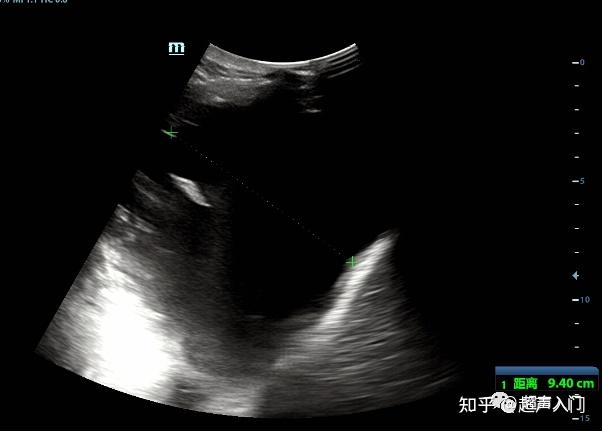

胸腔积液超声图像请教

图片尺寸844x562